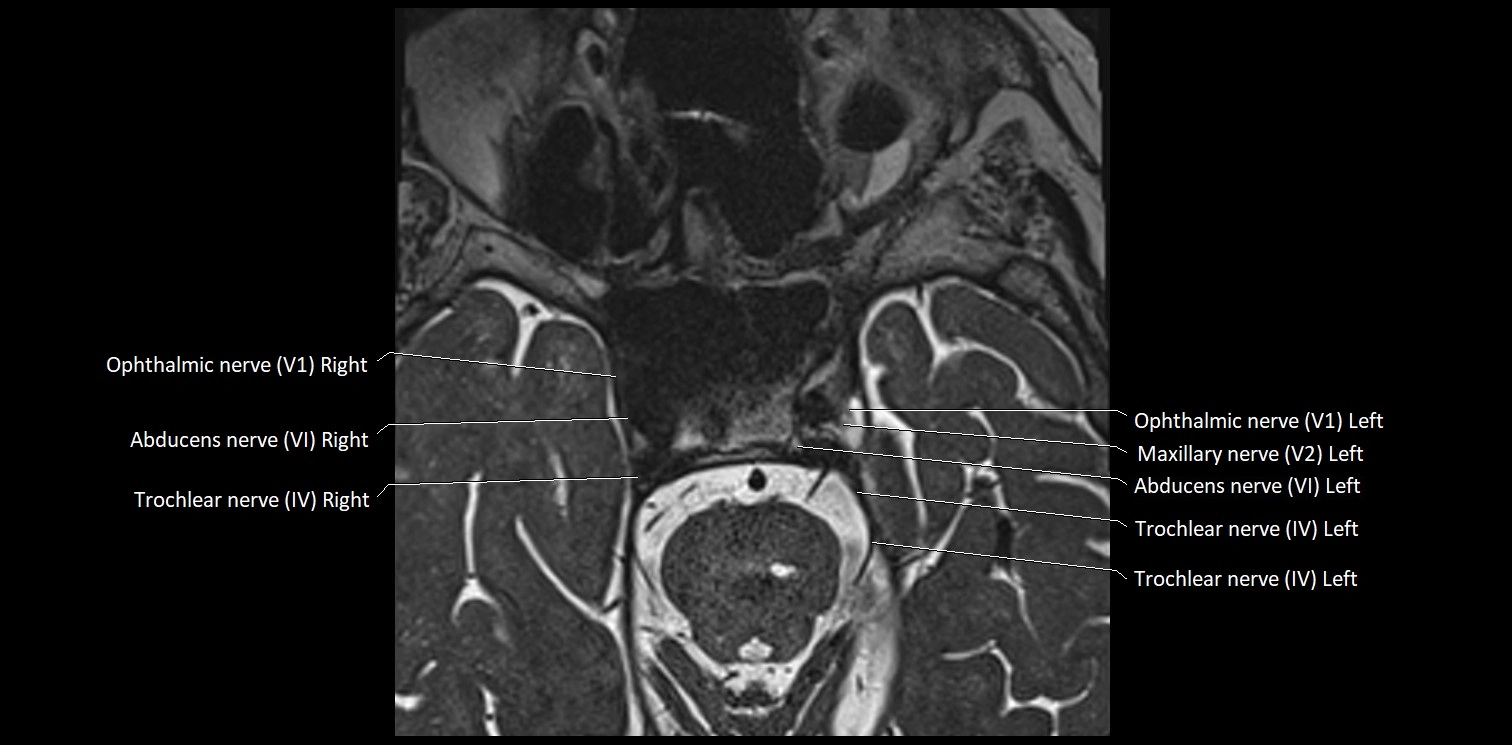

MRI Appearance

• The abducens nerve is a small, thin, linear structure

• Best visualized on high-resolution T2-weighted 3D MRI sequences (e.g., FIESTA or CISS)

• Seen as a hypointense (dark) line running from the brainstem at the pontomedullary junction, traversing the prepontine cistern, and entering Dorello’s canal under the petrosphenoidal ligament, then into the cavernous sinus, and finally the orbit

• May be challenging to visualize in standard MRI due to its small size

• Pathology may be inferred by absence, displacement, or enhancement of the nerve